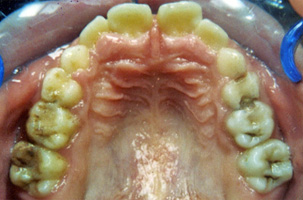

Περιοδοντολογία

Η περιοδοντική νόσος μετακινεί τα δόντια καθώς το κόκαλο που τα υποστηρίζει υποχωρεί σταδιακά. Έτσι τα δόντια εμφανίζουν διαστήματα μεταξύ τους ή/και περιστρέφονται. Η ορθοδοντική θεραπεία επαναφέρει τα δόντια στις ορθές τους θέσεις και τέλος τα ακινητοποιεί ώστε να διασφαλιστεί η μακροβιότητά τους στο στόμα.